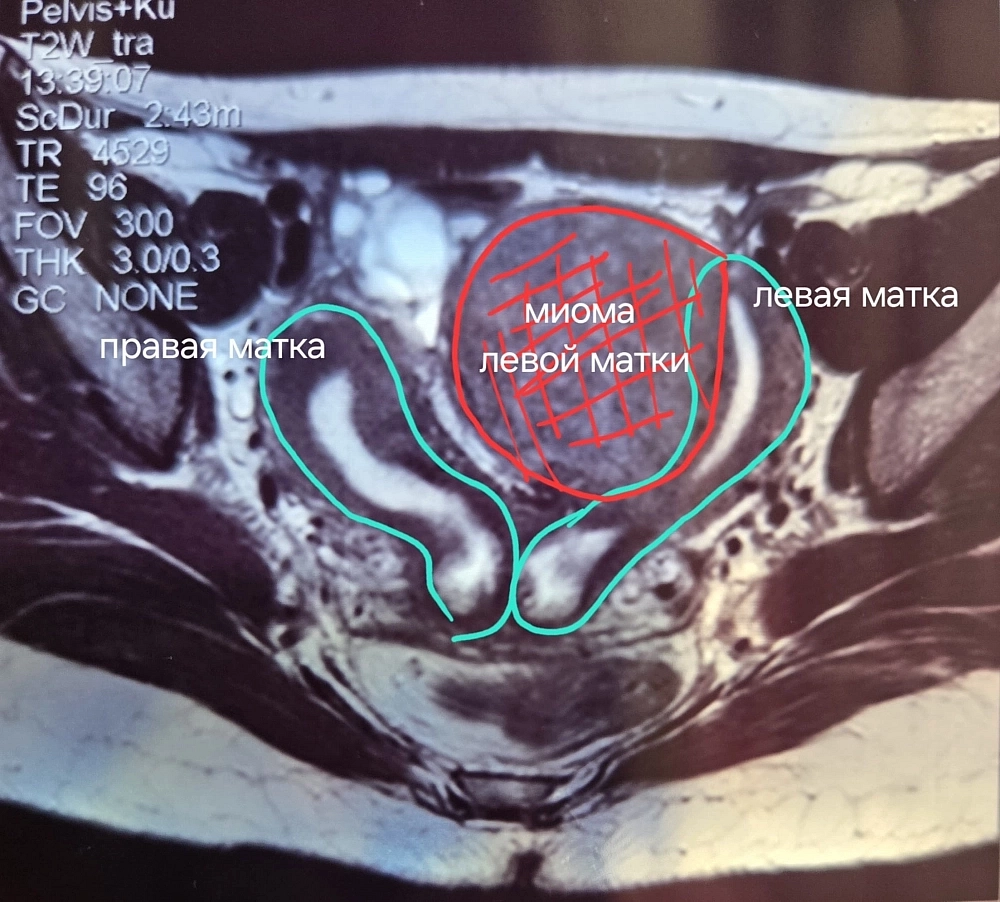

Огромная миома

Само по себе наличие двух маток — не повод ложиться под нож. Но у Ирины, как выяснили медики, на одном из органов появилась огромная миома — доброкачественное новообразование.

«Миома была выявлена на левой матке. Нашей задачей было сохранить пациентке репродуктивную функцию, удалить новообразование, а также провести реконструкцию женских органов. То есть из двух сделать одно, чтобы увеличить пациентке шансы на самостоятельную беременность», — прокомментировал Олег Юрьевич.

Диаметр опухоли составлял 6 см (почти как вся матка). Патология вызывала постоянные боли, а также дискомфорт во время женских дней.